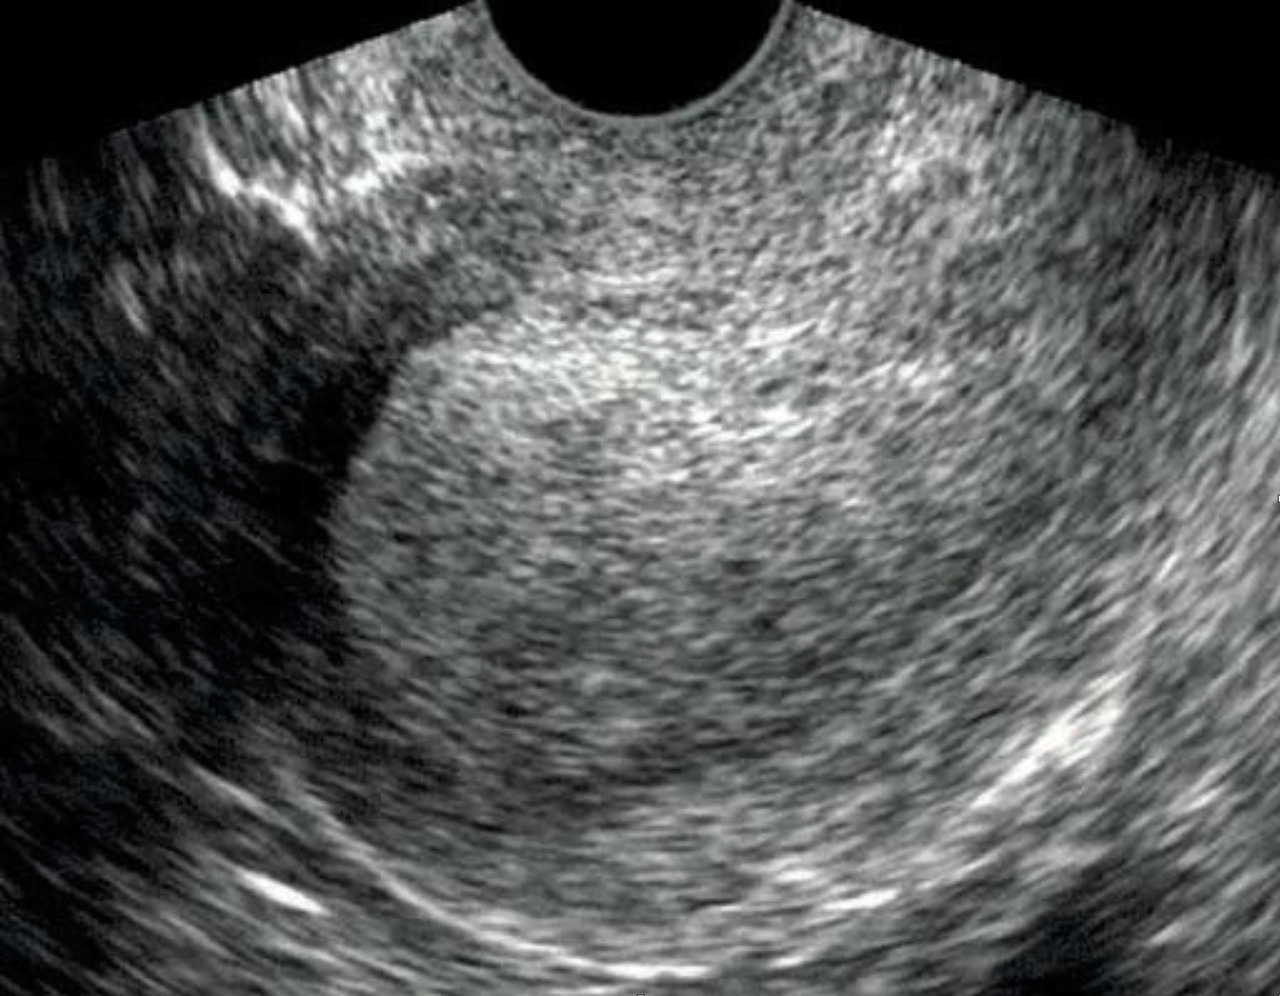

L’hyperplasie de l’endomètre correspond à des anomalies structurales endométriales aux frontières de la bénignité et de la malignité. Le diagnostic est histologique. On retrouve à l’échographie un endomètre épaissi (fig. 7). L’hystéroscopie met en évidence un endomètre épais et permet de diriger les biopsies. La classification de l’Organisation mondiale de la santé (OMS) de 1994, reconduite en 2003, subdivisait les hyperplasies endométriales en quatre groupes : les hyperplasies simples sans atypies, les hyperplasies complexes sans atypies, les hyperplasies simples avec atypies et les hyperplasies complexes avec atypies. La classification de l’OMS de 2014, reconduite en 2020, a simplifié cette classification et conservé uniquement deux groupes : les hyperplasies endométriales sans atypies et les hyperplasies endométriales avec atypies/EIN (Endometrioid intraepithelial neoplasia). Il a été démontré qu’hyperplasie atypique et EIN étaient sensiblement synonymes.

Le cancer de l’endomètre est la première cause à évoquer en cas de métrorragies post-ménopausiques. Ces métrorragies sont spontanées, indolores et de faible abondance. Il s’agit en général d’un adénocarcinome. L’interrogatoire recherche des facteurs de risque généraux (âge, diabète, hypertension artérielle [HTA], obésité), locaux (irradiation pelvienne, hyperplasie adénomateuse ou atypique) ou hormonaux (puberté précoce, ménopause tardive, nulliparité, estrogénothérapie de traitement hormonal substitutif, prise de tamoxifène). L’examen retrouve un utérus modérément augmenté de taille. Le diagnostic repose sur l’histologie. On peut réaliser une biopsie d’endomètre en consultation à la pipelle de Cormier ou à la canule de Novak qui n’a de valeur que si elle est positive. Le prélèvement histologique peut aussi être réalisé par curetage bio­psique ou sous hystéroscopie, permettant la visualisation directe des lésions et le guidage des prélèvements histologiques par résection. L’échographie pelvienne recherche un épaississement de l’endomètre (mesure des deux feuillets supérieure à 4 mm) ainsi qu’une irrégularité de celui-ci, avec une mauvaise visualisation de l’interface endomètre-myomètre.